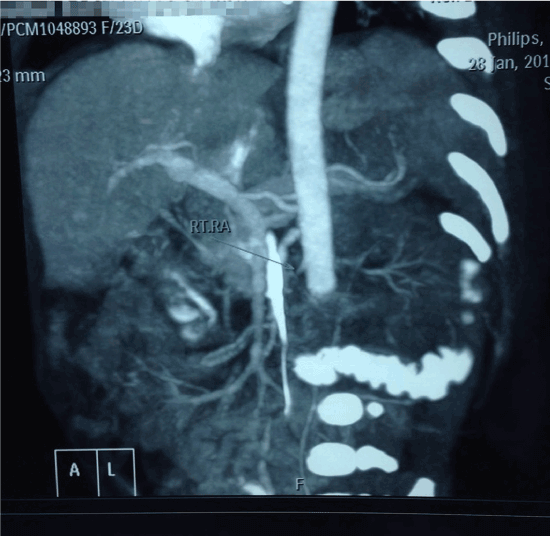

On further investigation there was a structurally normal heart. The USG Doppler study confirmed severely compromised lower limb circulation with possible intraluminal obstruction of the distal vessels supplying the lower limbs. Further imaging with CT angiography revealed a near complete obstruction of abdominal aorta distal to the origin of the renal arteries with a suspected intra-luminal thrombus (Figure 1). Failure of medical thrombolysis by systemic administration of high-dose Urokinase was followed by the decision of surgical exploration of the affected vessels. The affected vessels were explored through intra abdominal excision. The thrombus was removed with subsequent restoration of lower limb circulation.

Figure 1. Renal arteries with a suspected intra-luminal thrombus